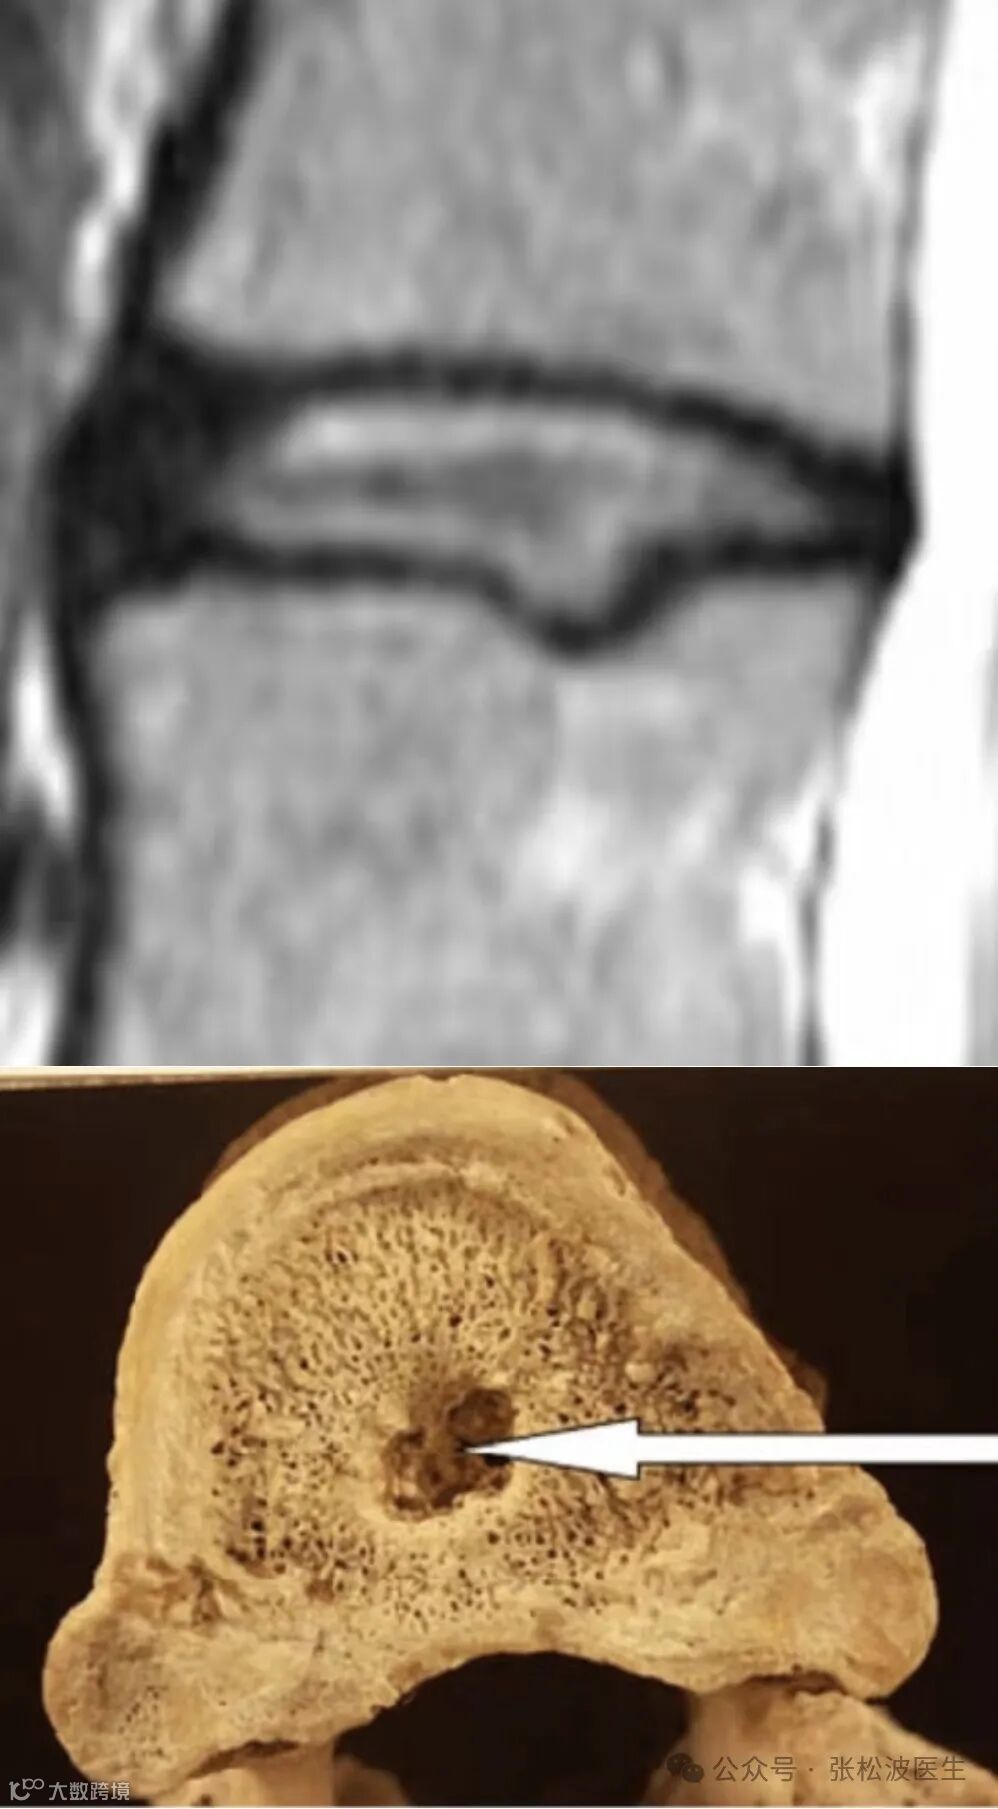

椎间盘内突